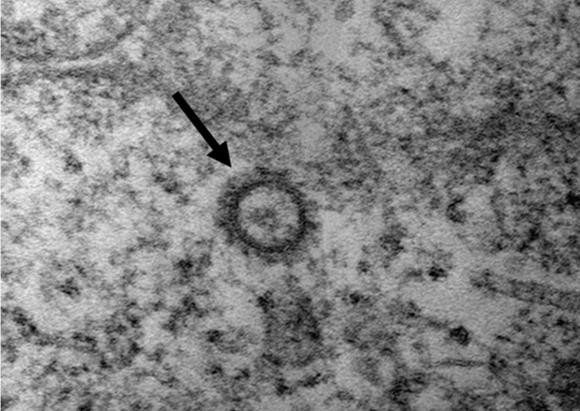

질병관리본부(본부장 정은경)는 27일 6명의 코로나19 환자로부터 얻은 바이러스 유전자를 분석한 결과와 고해상 전자현미경 사진을 공개했다.

코로나19 바이러스(SARS-CoV-2)의 전자현미경 사진. ⓒ 질병관리본부

정은경 질병관리본부 본부장은 고해상 전자현미경 사진을 공개하면서 "현재 바이러스 특성 분석을 진행하고 있으므로, 예방과 대응을 위한 보다 상세한 분석결과가 곧 제시될 수 있을 것"이라고 말했다.